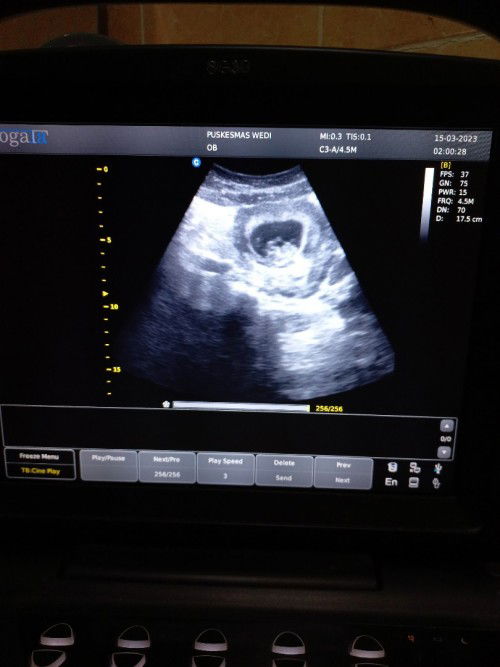

Jadi barusan hari ini aku usg di puskesmas, usia pas 10 minggu, tapi bentuk janinnya seperti ini normal tidak ya, soalnya waktu 8 minggu bentuknya lebih keliatan dari pada yang 10 minggu, mohon tanggapannya bun, itu normal tidak ya, kata ibunya normal, cuma kurang yakin aja gitu..#seriusnanya #bantusharing #ingintahu